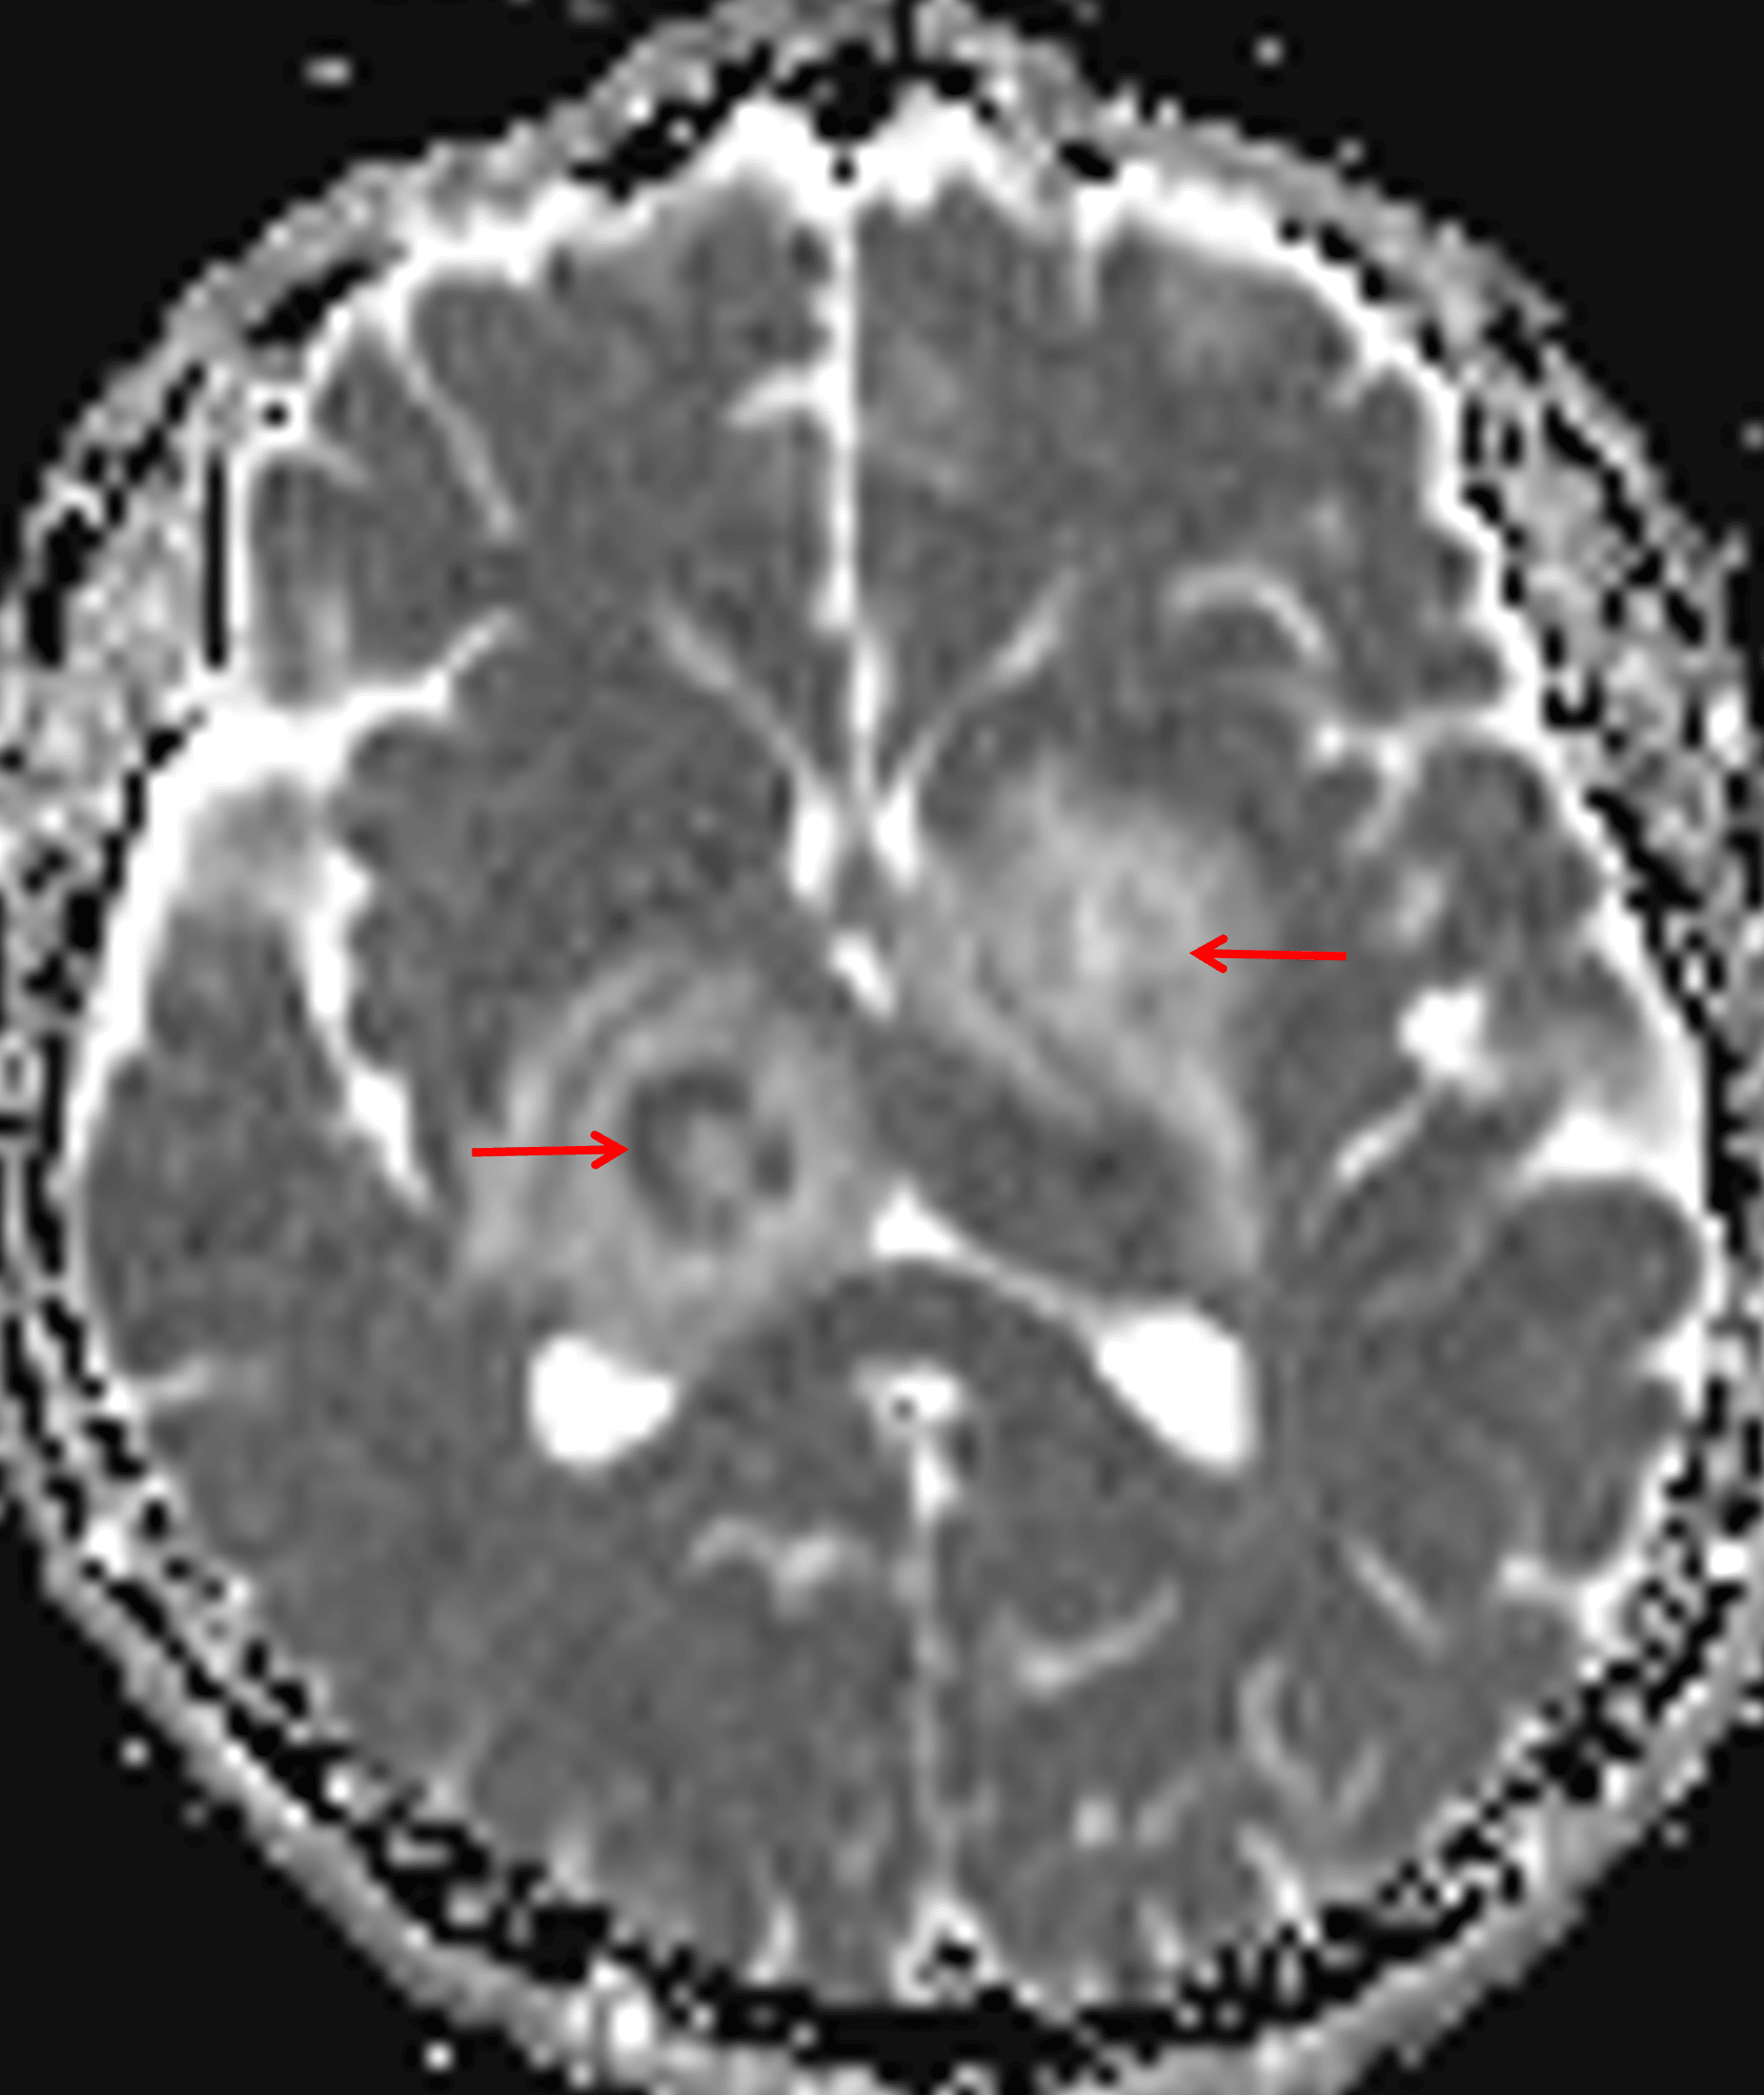

Peripheral restricted diffusion, more pronounced with the right thalamic lesion (red arrows).